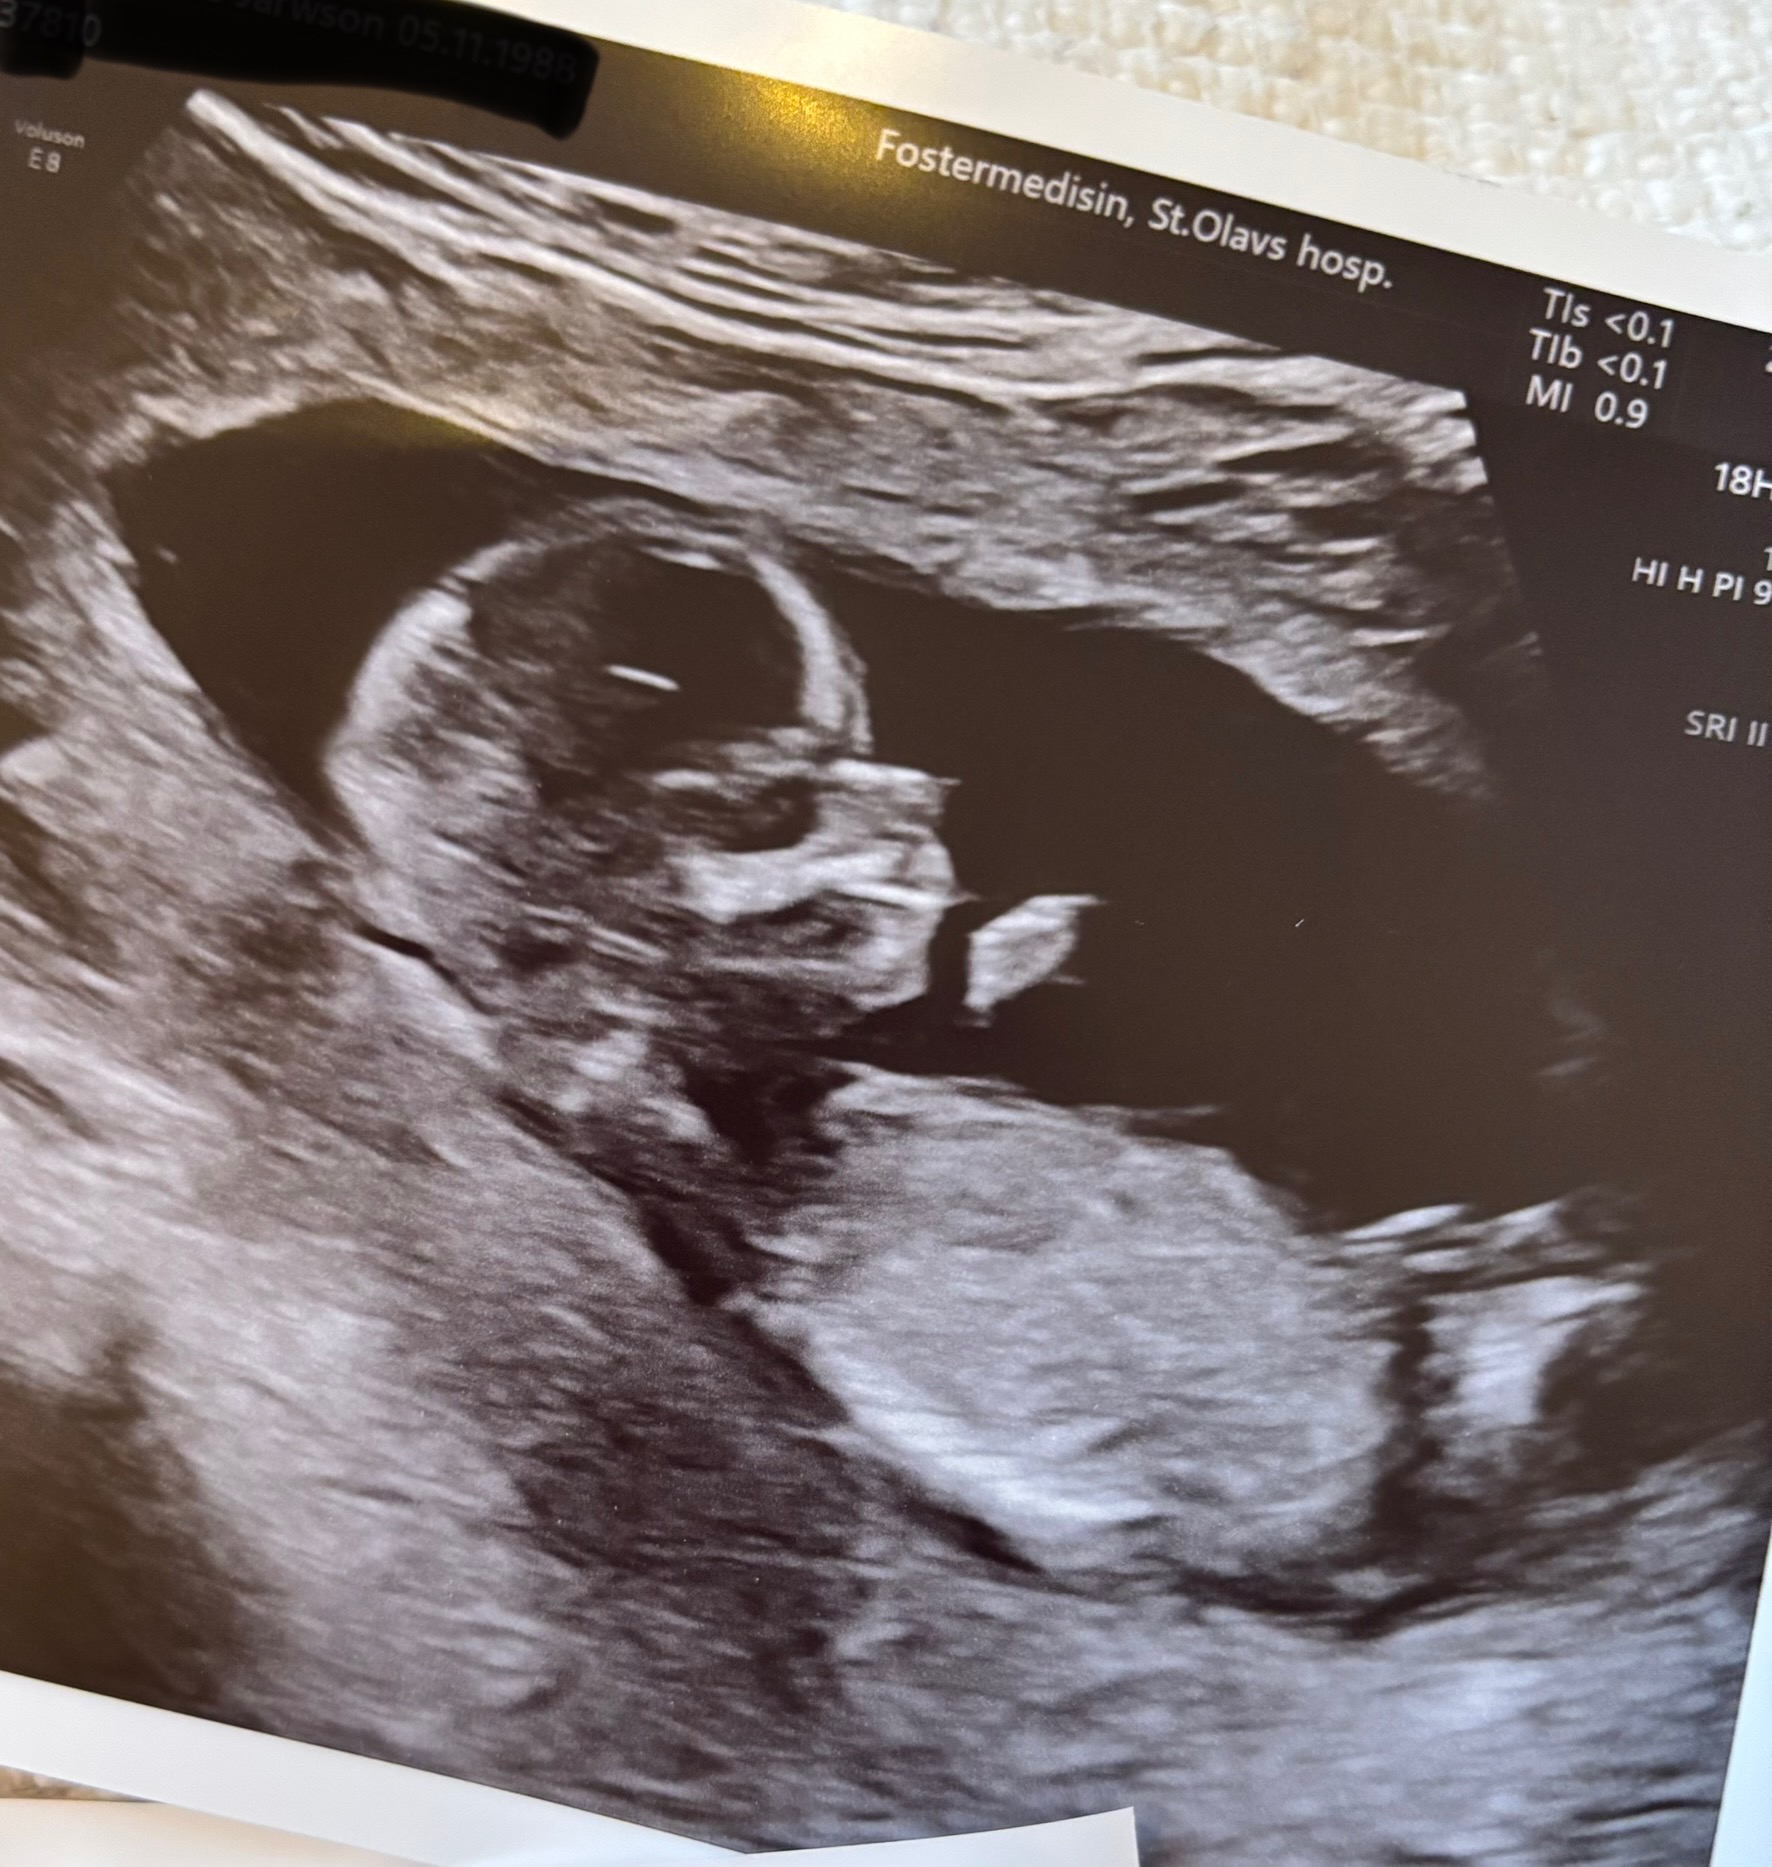

Plutselig hadde jeg fått svar fra fostermedisin: der så alt normalt ut, med lav sannsynlighet for alle tre trisomier!!

Jeg hadde kjøpt et fint antrekk i gave til henne, og inni der lå en pakke til, og der inni lå en baby-onesie! «Babyklær?!» sa hun, så undret vi på hvorfor hun fikk det i gaven sin, men hun skjønte med en gang at vi skulle få baby! Også hadde jeg laget en konvolutt med UL-bildet og en tegning av oss med baby i magen. Så spurte hun om babyen på UL-bildet var en baby inni magen nå, så ble hun superstolt og smilte fra øre til øre og forteller nå alle hun møter på at «mamma har en baby i magen sin»